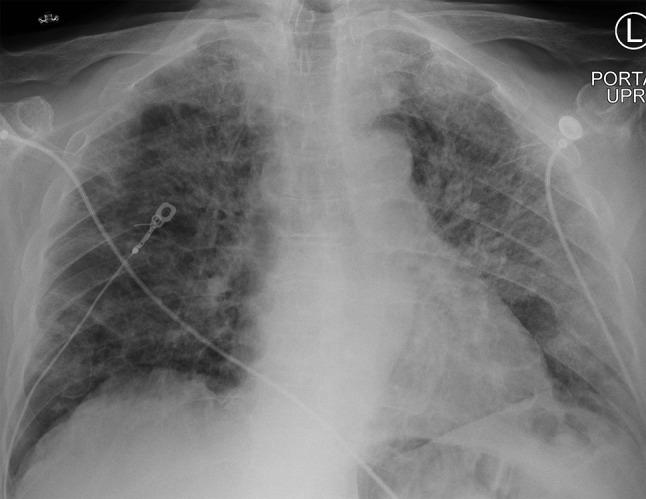

An 80-year-old male with recently diagnosed multiple myeloma undergoing treatment with lenalidomide and daratumumab presented with acute, rapidly progressive hypoxic respiratory failure ultimately requiring intubation and mechanical ventilatory support. Imaging revealed bilateral pulmonary opacities, however infectious workup was negative, and he was ultimately diagnosed with lenalidomide-induced interstitial pneumonitis, a rare but serious adverse effect of this medication. He was treated with drug discontinuation and methylprednisolone, and quickly recovered.

Lenalidomide is an immunomodulating medication used in the treatment of multiple myeloma, and is associated with rare but serious cases of drug-induced interstitial pneumonitis. Thus, if a patient receiving lenalidomide develops shortness of breath and/or hypoxia, drug-induced pneumonitis must be on the differential. Permanent drug discontinuation with or without corticosteroids is the mainstay of treatment, and patients are often able to fully recover, underscoring the need for early recognition of this condition.